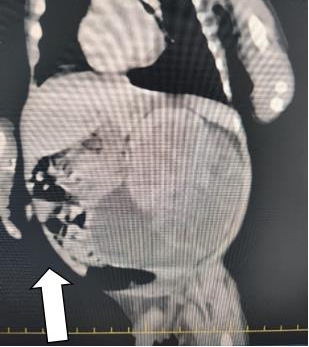

A 29-year-old pregnant woman with no prenatal follow-up was found to have polyhydraminosemia on prenatal ultrasonography and the baby was found to have an abdominal mass and dilated intestinal loops. The patient was born at 39 weeks of gestation at 3490 grams by cesarean delivery. APGAR at the 1st minute of delivery was 7 and APGAR at the 5th minute was 8. The patient who underwent positive pressure ventilation after delivery was admitted to the neonatal unit with the diagnosis of respiratory distress and intraabdominal mass. On physical examination, abdominal distension was present and the traube area was closed as pathologic findings. In addition, there was a 9x5 cm mass to the left of the umbilicus consistent with left kidney localization. Whole abdominal ultrasonography of the patient revealed a 90*48 mm mass lesion in the left renal lobe with a relatively smooth bordered mass lesion with solid and cystic components. Contrast-enhanced abdominal CT was performed for further examination. Contrast-enhanced CT scan was reported as a 9x6 cm space-occupying lesion with cystic and solid components in the left renal lobe (Figure 1).

Image 2: Abdominal CT, 9x6 cm cystic space-occupying lesion with solid components in the left renal lobe